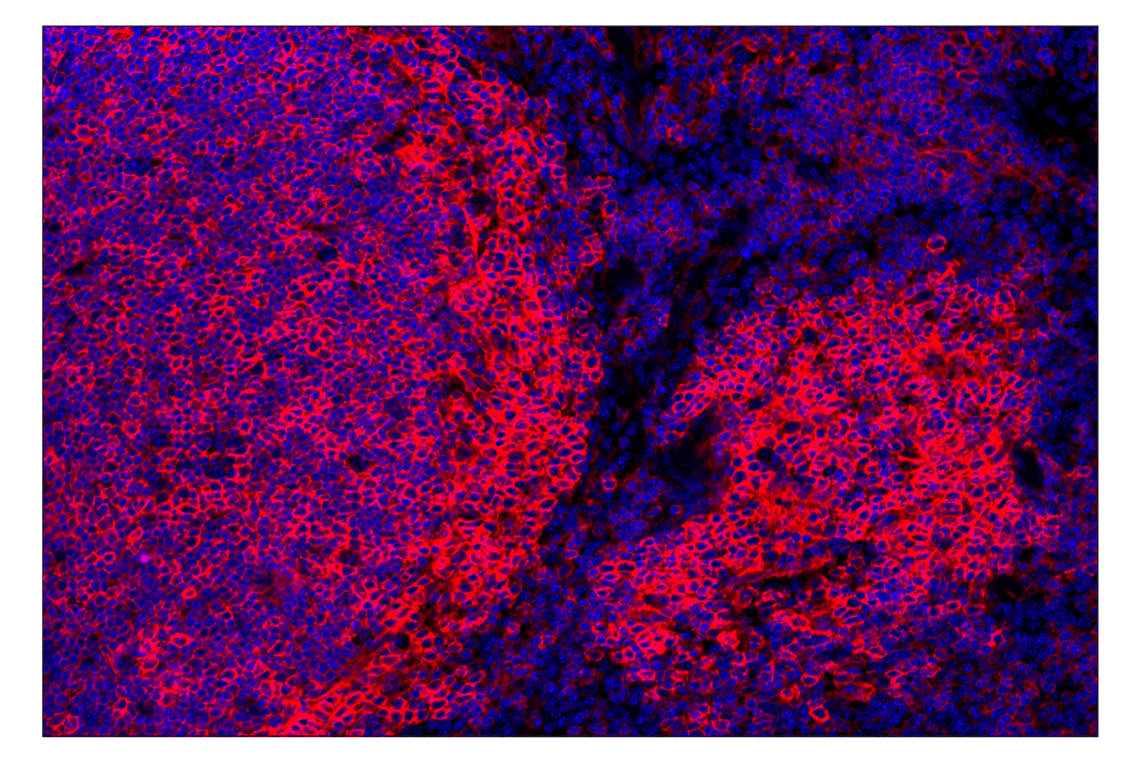

CD38 (E9F5A) Rabbit Monoclonal Antibody (Alexa Fluor® 555 Conjugate) #52005

Immunohistochemistry (Paraffin) 1:100 - 1:400

CD38 (E9F5A) Rabbit Monoclonal Antibody (Alexa Fluor® 555 Conjugate) recognizes endogenous levels of total CD38 protein.

Monoclonal antibody is produced by immunizing animals with a synthetic peptide corresponding to residues surrounding Pro298 of mouse CD38 protein.